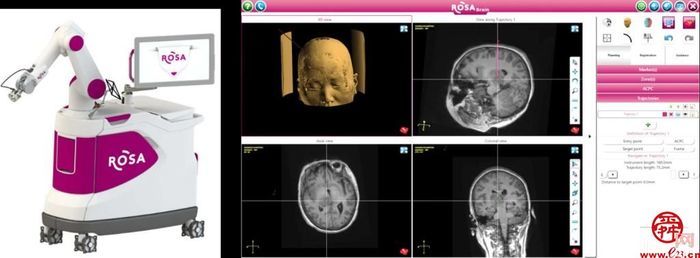

图1多模态影像支持下设计穿刺路径,避开血管及重要功能区,到达靶点

ROSAONE为最新一代ROSA机器人,为山东省内首台,国内第8台,在原有基础上精度提高50%,其激光注册定位精度在1mm以内,骨性标志注册定位精度小于0.4mm,可以满足包括脑深部病变活检、DBS、SEEG、脑血肿穿刺引流等神经外科各类精准手术需求。头皮切口仅0.5cm,手术创伤小,术后恢复快。同时,其机械臂活动范围增加近30cm,更高的精确度和灵活性可以更好地进行多角度探测及定位。